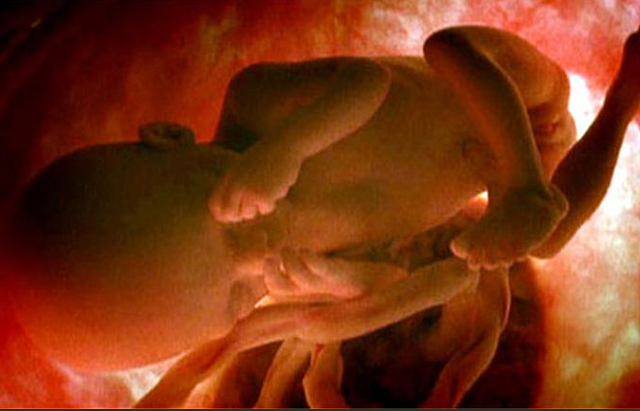

En la 9 semana del embarazo tu bebé,que en este momento se conoce como feto, ahora que la cola del embrión ha desaparecido,en esta semana ya comienza a estirarse y enderezar su tronco y este bebe mide cerca de 2,5cm de largo.

En la 10 semana del embarazo el bebe ya a pasado de embrión a feto .Y es que va a haber mucho cambiado en su desarrollo se comienza a ver muy claramente que es un ser humano a simple vista por su tamaño y peso.Las medidas del bebé rondan los 4 centímetros y su peso es de 5 gramos.

A la semana 11 del embarazo el bebé pesa aproximadamente 8 gramos y su tamaño será entre 4 y 6 centímetros. Vamos a poder ver grandes cambios a partir de ahora, sus dedos ya los podrán ver separados gracias a que las membranas que los unían han desaparecido.

El bebé ya se mueve dentro de la mujer y ya es capaz de estirarse y dar pequeñas pataditas. Si es el primer embarazo aún es pronto para que las mujeres noten esta sensación de hormigueo . Pero las mujeres que ya tienen su segundo embarazo ya pueden sentir esta sensación alrededor de las 12 semanas. Él bebe ya puede tener 10 semanas de vida y mide 6,5 centímetros y pesa 18 gramos. Él bebe ya se pude alimentar a través del cordón umbilical, recibiendo ya nutrientes y oxigeno

El bebe en estas semanas ya se le podrán ir formando mejor los órgano y su cabeza todavía no tendrá forma ,aunque en estas semanas ya comenzara a funcionar el sistema nervioso y pesara 20 a 25 gramos, medirá de 7 o 8 cm

Este bebé sigue desarrollándose dentro del útero. Ahora ya mide aproximadamente 9 a 10 cm y pesa unos 50 gramos. Para que tengas una idea de su tamaño, su fémur tiene un tamaño de 1,8 cm, es que así este bien formado y se vea bien en la ecografías ya se ve como una personita, aunque todavía es muy pequeñito

En esta semana El feto mide entre 10,8 a 11,6 centímetros y pesa 80 gramos ,el bebe ya tendrá todo su cuerpo incluida su cabeza, está recubierto de ese pelo tan fino, Las primeras zonas en las que el bebé empieza a tener pelo son las cejas y sobre el labio superior. Tras el nacimiento, este pelo se cae y empieza a crecer otro más grueso que nace de nuevos folículos pilosos. Al bebe ya se lo comenzaran a formar las uñas de los dedos y pies ,se diferencian las uñas de los dedos

El cuerpo del bebe está recubierto de grasa, se mueve con fuerza dentro del útero. La embarazada puede notar dolor abdominal a medida que el útero crece, la dieta materna es muy importante para el correcto desarrollo del feto.El bebé mide entre 11 y 13 centímetros y pesa unos 100 gramos en la semana 17 de embarazo. Cada vez su aspecto es más parecido al de un recién nacido, El tejido adiposo es importante para mantener el calor corporal y regular el metabolismo del organismo.

En la semana 18 del embarazo, en este momento en que el bebé lleva 16 semanas formando, mide unos 13-15 cm y pesa cerca de 150 gramos. Además, en esta semana ya empiezan a formarse las huellas dactilares del bebé, y también el bebe ya comienza a escuchar sonidos

El bebé mide alrededor de 15 cm y pesa unos 250 gramos. Su cabeza, brazos y piernas ya tienen un tamaño proporcionado con el resto del cuerpo y ha comenzado a crecerle pelo en la cabecita. Las orejas y los ojos ya casi se ubican en su posición final. Algo asombroso, pero si la mujer está esperando una niña, sus pequeños ovarios que no tendrán más tamaño que el de un botón ya contienen huevos primitivos que darán origen a los óvulos.

En la semana 20 de embarazo (18 desde la fecundación) el bebé mide 16 centímetros y alrededor de 350 gramos. En estos momentos de la semana sus pulmones comienzan a practicar el ejercicio de la respiración y su sistema digestivo hace lo propio tragando líquido amniótico, absorber los nutrientes de este líquido en el intestino delgado y pasar el resto de su contenido al intestino grueso.

En la semana 22 de embarazo el bebé mide 27 centímetros y pesa casi 500 gramos. Se pueden percibir sus párpados, uñas y cejas, aunque estas últimas todavía no tienen color, son unas pelusillas blancas que se ven encima de los ojos.

Tu bebé en esta semana mide 28 centímetros de la cabeza a los pies y pesa poco más de medio kilo.Se puede notar que su piel es una fina capa que recubre su cuerpo, pero ya no es traslúcida, sino que empieza a verse rojiza y arrugada. Las capas de grasa irán depositándose debajo de la piel.

En la semana 24 de embarazo, el bebé mide 29-30 centímetros y pesa entre 630-680 gramos aproximadamente. A partir de las 24 semanas de embarazo, si tuviera en lugar un parto prematuro, tendría probabilidades de sobrevivir el bebe con cuidados intensivos.

Ya el bebe en esta semana ya le mide la columna 21cm hasta la cabeza ,pesa 700 gramos y puede sonreír, bostezar y su lengua ya puede salir de su boca.

En la semana 26 de embarazo, el bebe ya mide unos 35,6 centímetros, desde la cabeza hasta el coxis, y pesa unos 760 gramos.

A partir de la semana 27, empieza el tercer y último trimestre del embarazo. El bebé ya pesa en torno a 1 kilo y la longitud total de la cabeza a los pies es de unos 34 centímetros. Los movimientos fetales son más fuertes y pueden llegar a hacerle daño a la mama o mujer.

En estas semanas de embarazo el peso del bebe es de unos 1.100 gramos y la longitud total llega a los 35 o 40 centímetros de la cabeza a los pies. El sistema nervioso central se está desarrollando mucho en estas semanas de gestación.

El bebe ya pesa unos 1.350 gramos y mide unos 38 centímetros de la cabeza a los pies con 30 semanas de embarazo. Si todo transcurre con normalidad, la futura madre tendra que ir al ginecólogo hasta la semana 36 de embarazo, ya que las citas se dan cada cuatro o seis semanas.

En la semana 31 de embarazo, pesa entre 1.600 y 1.700 gramos aproximadamente y mide alrededor de 41-42 centímetros. Alrededor de la semana 31 de gestación, los bebés suelen colocarse ya en posición cefálica, la más idónea para nacer y si eso ocurre notarás ya sus movimientos en la parte alta del abdomen.

El bebé pesa en la semana 32 de embarazo entre 1,8 y 2 kilos aproximadamente, y mide entre 38 y 43 centímetros. Ahora se cree que el bebé dentro del útero puede pensar, e incluso crear su primer recuerdo a partir de la semana 32.

En la semana 33 de gestación,mide unos 43-45 cm y pesa cerca de 2.000 gramos. El cerebro del bebé sigue desarrollándose y ahora ya tiene los cinco sentidos preparados para cuando baya que nacer.

El bebé mide aproximadamente 46 centímetros y pesa alrededor de 2,200 gramos. Sus pulmones ya están casi completamente formados y sus huesos se han ido endureciendo pero todavía son muy flexibles, incluidos los de la cabeza.Su cráneo todavía no está completamente cerrado, lo cual le permite adaptarse con mayor facilidad al canal de parto en el momento de nacer. Por eso, algunos bebé nacen con la cabeza en forma de cono o aplastada, pero esto se revierte a los pocos días de nacer.

Los pulmones del bebé acaban su proceso de maduración. Pero se debe estar pendiente de signos de parto prematuro (contracciones , sangrado vaginal o rotura prematura de membranas) porque todavía es pronto para dar a luz. Notarás mucha presión del bebé en la pelvis y la vulva e incluso calambres en la vagina. El bebé pesa unos 2.500 gramos y mide alrededor de 45 centímetros en la semana 35 de embarazo. A partir de ahora, los pulmones del bebe ya están maduros.

En estas semanas el bebé pesa unos 2.750 gramos y mide 46 centímetros . En estas semanas de gestación todavía se le considera un feto prematuro. El bebé sigue moviéndose, lo notarás a diario, pero es raro que logre darse la vuelta dentro del útero materno.

En estas semanas de gestación deben estar muy atenta a las contracciones de parto.En estas semanas del embarazo empieza la cuenta regresiva hasta la meta del embarazo que es el momento del parto

El bebé en la semana 40 de embarazo mide entre 48 y 51 centímetros de la coronilla a las nalgas, y el peso se sitúa alrededor de los 3500 gramos.Lo que está claro es que, cuanto más nos alejemos de la fecha prevista del parto, más probable es que el bebé pese más.